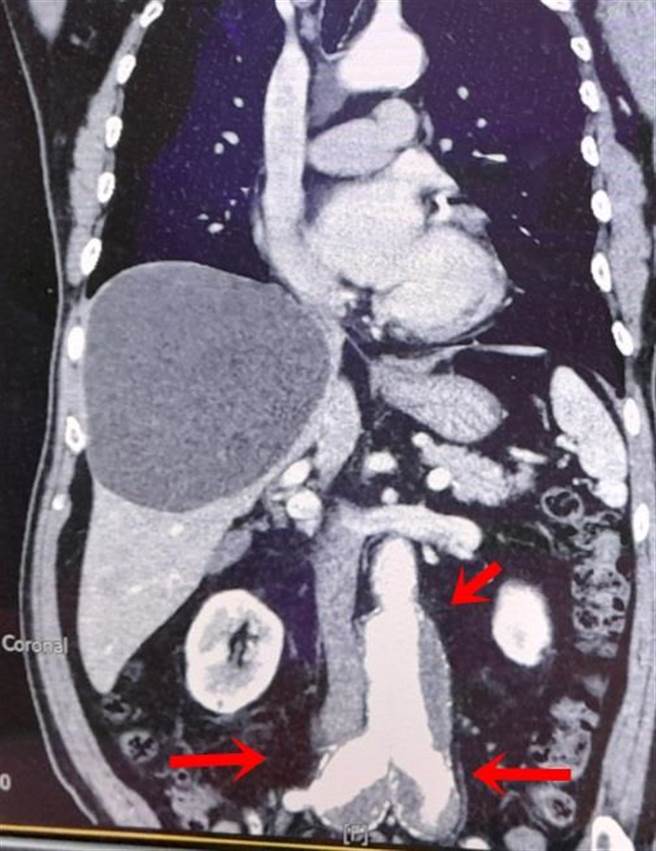

71岁刘先生罹患肺癌,肾臟功能也不佳正在治疗中。他因腹胀、食欲不振、体重骤降,到童综合就医检查,赫然发现肾臟下有直径6公分腹主动脉瘤,双侧总肠骨动脉也各有4公分动脉瘤,随时都可能破裂而瞬间危及生命。童综合医院安排病人至复合式手术房进行微创腹主动脉瘤血管内支架修补手术,以及肠骨动脉血管支架置放手术,术后隔天可下床走动,住院4天即返家休养。

由于个案患有多重疾病,竟又在腹主动脉与两侧总肠骨动脉都长出动脉瘤,分别有6公分与4公分大小,随时都有破裂的危险,所以需儘快进行手术治疗。以前作法是保留一侧内肠骨动脉,另外一侧内肠骨动脉要做栓塞处理,手术时间长而且会影响骨盆腔器官血流。

健保署于2010年通过肠骨动脉支架,简称IBE(iliac branch endoprosthesis),可让病人双侧内肠股动脉都保留,缩短手术时间也不影响骨盆腔器官血流。安排在复合式手术室直接进行血管摄影,从会阴处切开两个1公分伤口,然后将人工血管支架经血管摄影导引,顺着血管置入至病变处。